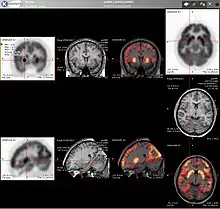

![]() Typical |